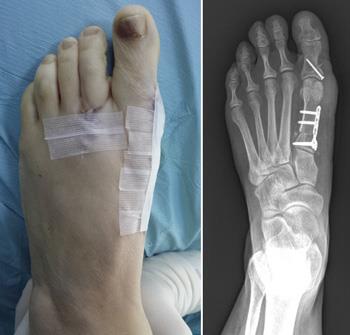

Because bunions vary in shape and size, there are different surgical procedures performed to correct them. In most cases, bunion surgery includes correcting the alignment of the bone by cutting and shifting the bones. This will most likely require the placement of surgical hardware (plates and screws) as well as repairing the soft tissues around the big toe.

In an osteotomy, your doctor makes cuts in the bones to realign the joint. After cutting the bone, your doctor fixes this new break with pins, screws, or plates. The bones are now straighter, and the joint is balanced.

Your sutures (stitches) will be removed about 2 weeks after surgery, but your foot will require continued support from dressings or a brace for 6 to 12 weeks.

Some bunion procedures allow you to walk on your foot right after the surgery. In these cases, patients must use a special surgical shoe to protect the bunion correction.